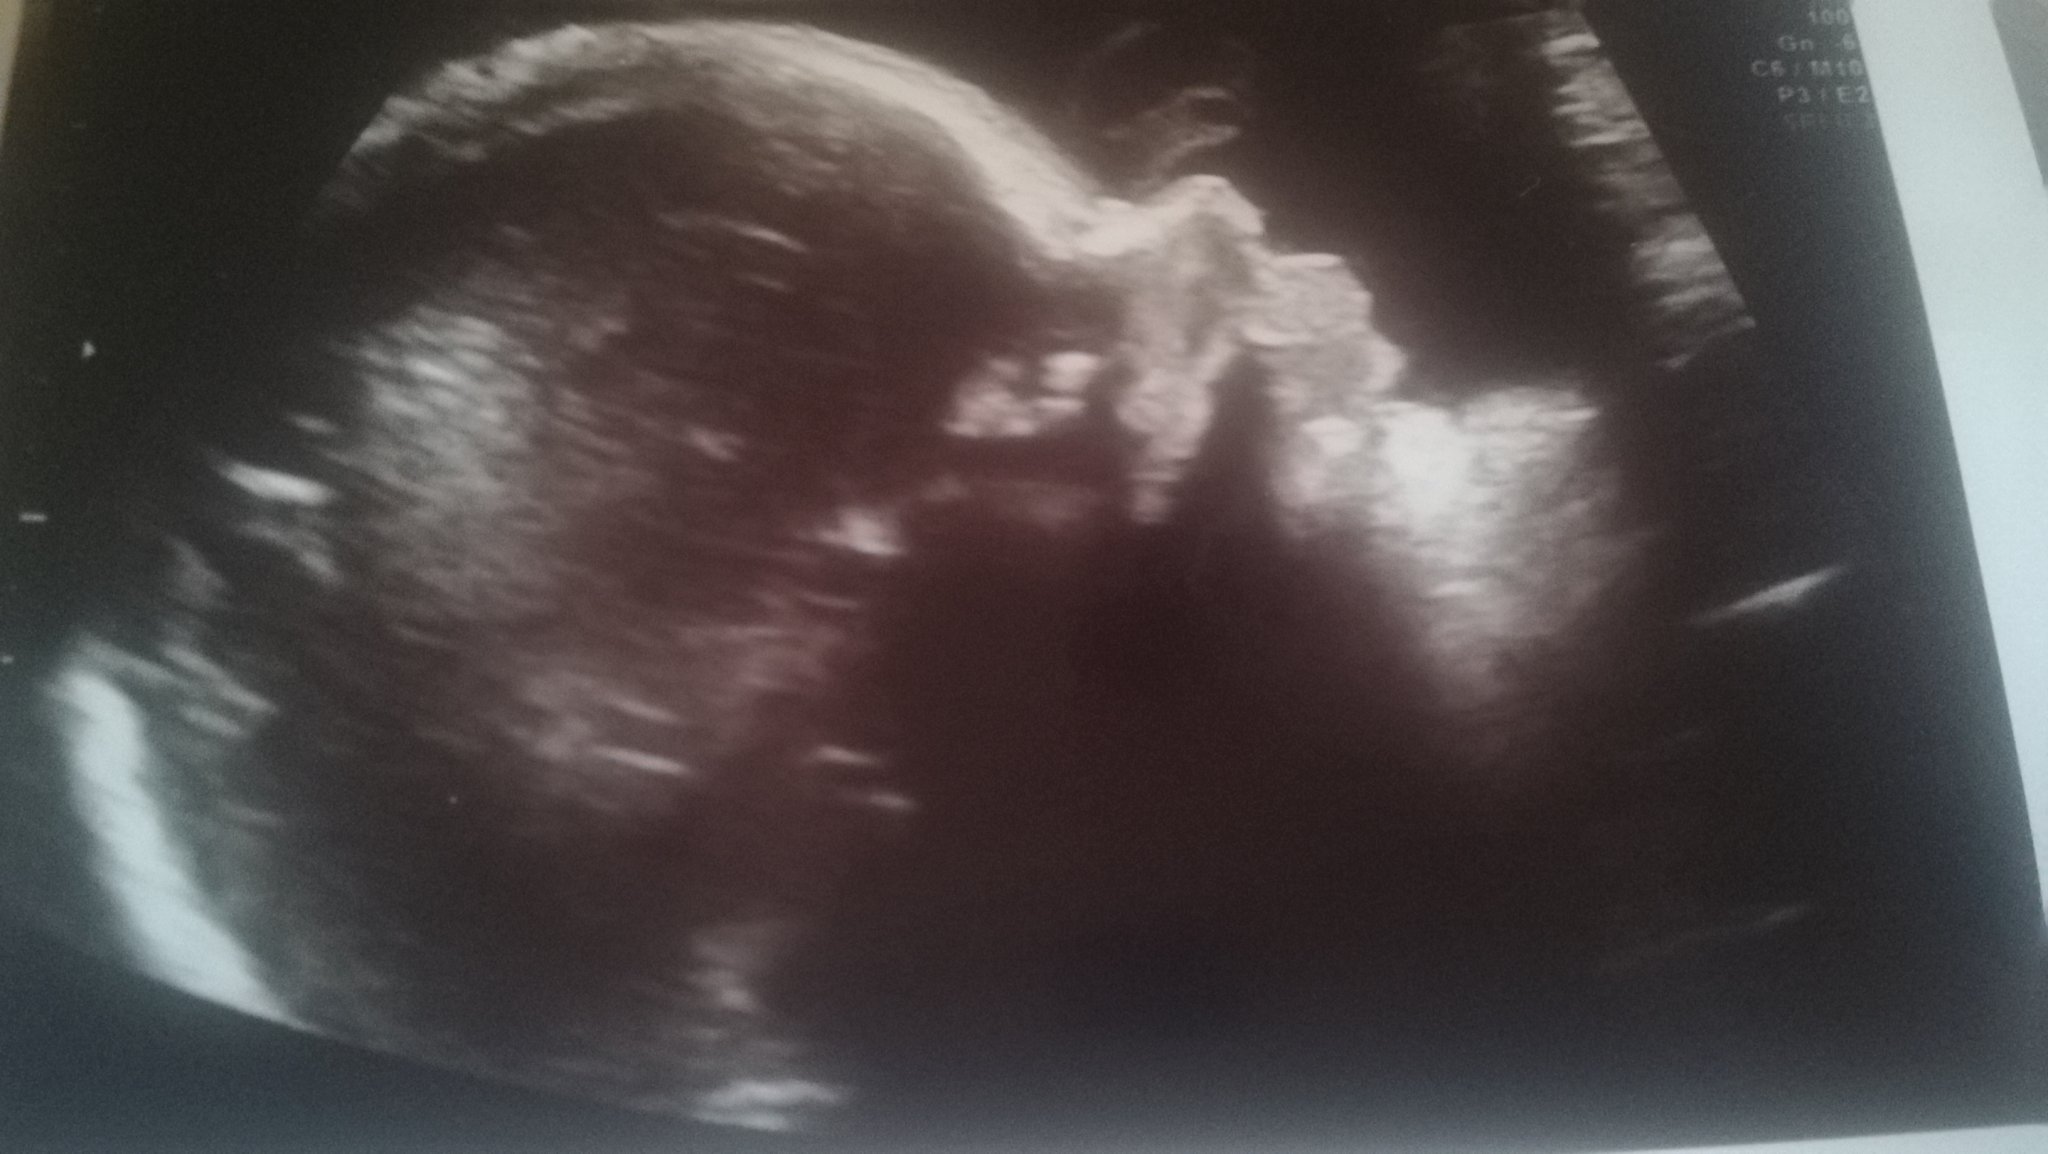

Форумът обсъжда теми, свързани с бременността, бебето и детското здраве. Участниците споделят лични истории, преживявания и се подкрепят взаимно в борбата с бременността и родителството. Форумът също така обсъжда теми, свързани със зачеването, изследванията, лечението и емоционалните преживявания на жените по време на процеса на опит за зачеване или след аборт. Също така се споделя информация как да се справим със загуби, проблеми по време на бременността и подкрепа в трудни моменти.